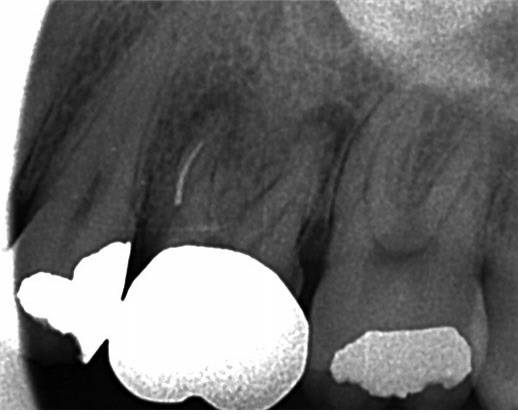

NiTi 전동 파일(이하 NiTi 파일)은 연속회전에 의해 삭제 효율이 높고 잔사제거가 우수하여, 근관치료에서 NiTi file의 사용은 당연한 것이 되었다. 그럼에도 간혹 급작스럽게 발생하는 파일 분리(file separation)는 NiTi file을 사용하는 치과의사들에게 항상 고민이 된다(그림1).

제거는 되지 않지만 파절편 주변으로 #8이나 #10 크기의 작은 기구가 들어가게 되면(by pass) 그 주변으로 충분한 세척과정을 거치고 통상적으로 근관치료를 마무리 한 후 follow up 한다 (그림 2). 간혹 우회조차 되지 않았지만 증상 완화 후 파절편 깊이까지 근관 충전하여 치료가 잘 마무리 되는 경우도 있다.